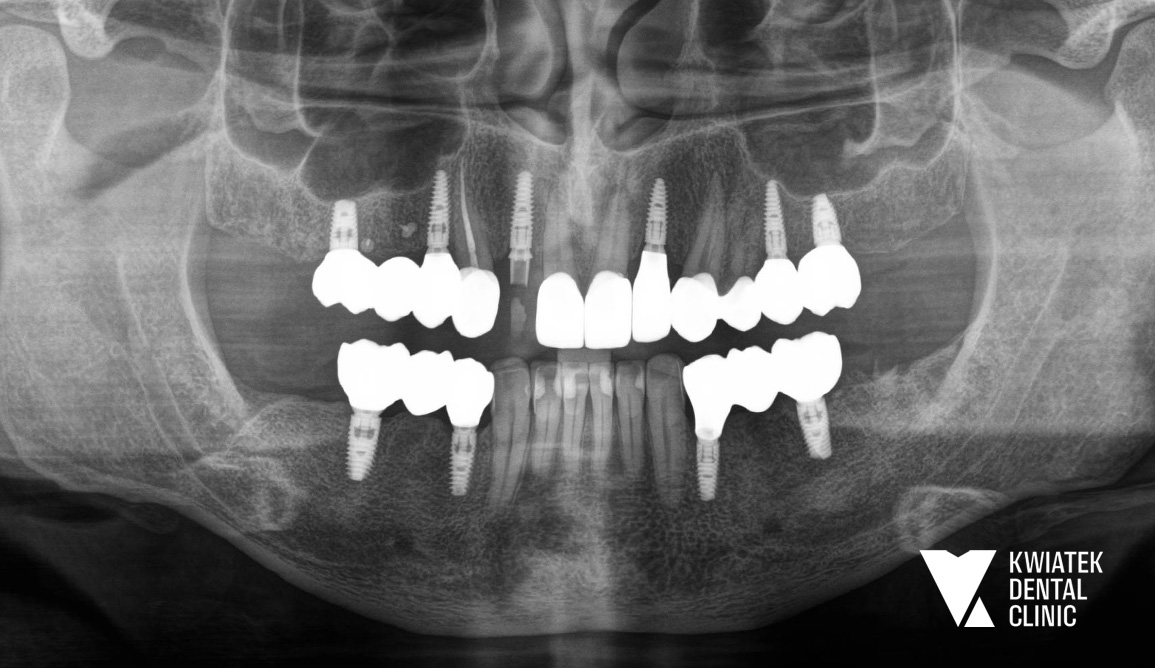

PO

Po integracji implantów wykonano korony ceramiczne na implantach oraz korony pełnoceramiczne na zębach własnych, dzięki czemu cały uśmiech zyskał harmonijny, estetyczny wygląd.